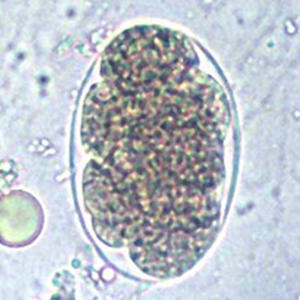

Les œufs de Necator americanus possèdent les caractéristiques morphologiques des œufs d’ankylostomes. Ils sont indifférenciables des œufs d’Ancylostoma à l’examen coproscopique (Strait et al., 2012).

Il comprend les nématodes du genre Ancylostoma et, de façon plus générale, tout œuf de strongle non embryonné.